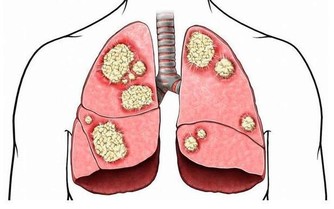

當年紀漸大,血管內膜會慢慢增厚,形成「斑塊」,動脈狹窄,導致心管阻塞。

過去,這樣的心血管疾病好發於老年人,然而隨著生活、飲食型態改變,疾病好發年齡層逐年下降,當斑塊結在血管分支的路口,血流過不去,容易發生閉塞,後果將不堪設想。